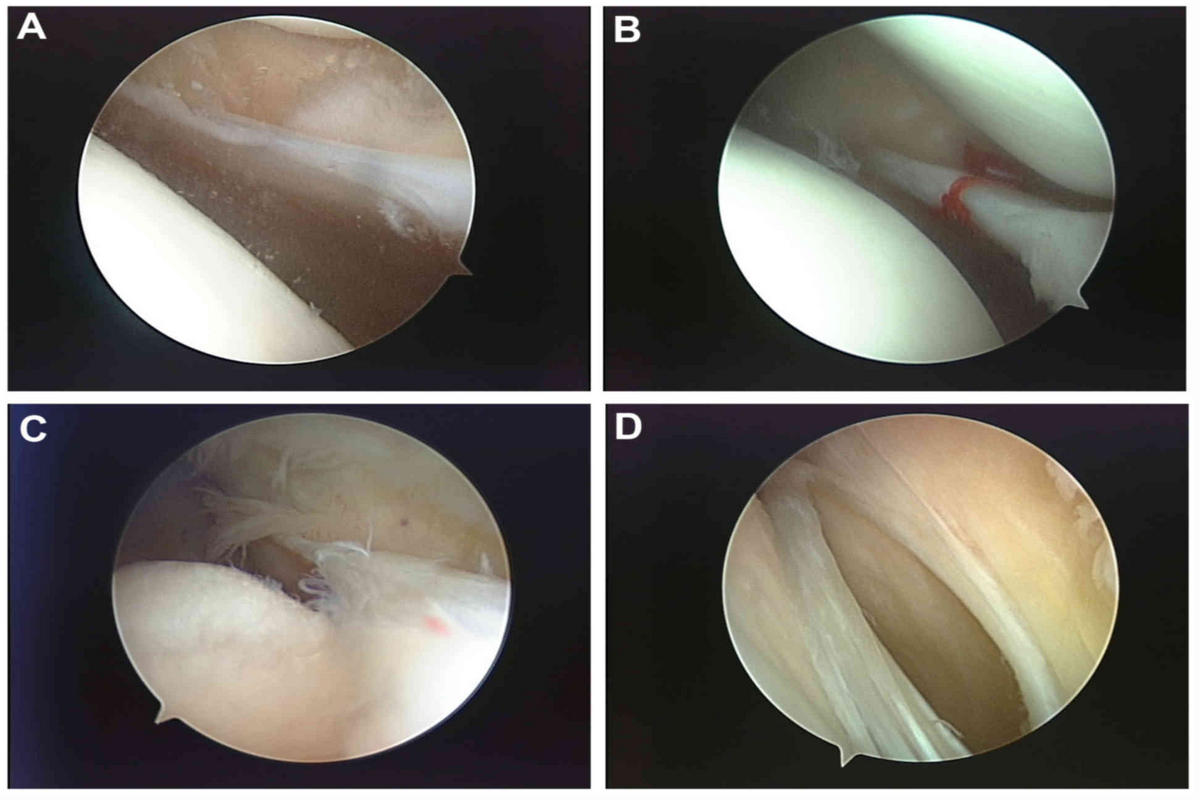

• Σε επιλεγμένες περιπτώσεις, η διάγνωση επιβεβαιώνεται με αρθροσκόπηση

Αρθροσκοπική αφαίρεση υμενικής πτυχής

Σε περιπτώσεις όπου τα συμπτώματα επιμένουν παρά τη συντηρητική αγωγή, ενδείκνυται αρθροσκοπική εκτομή της υμενικής πτυχής.

Η επέμβαση είναι ελάχιστα επεμβατική, με υψηλά ποσοστά επιτυχίας και ταχεία επάνοδο στις καθημερινές δραστηριότητες.